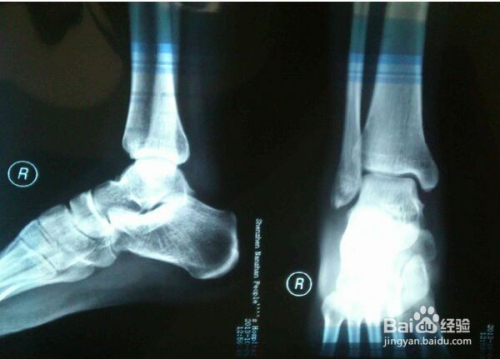

✨ 寻求专业帮助,科学治疗脚伤

脚受伤后,我第一时间去医院寻求了专业医生的帮助,医生对我的伤势进行了详细的检查,并给予了我专业的治疗建议,在治疗过程中,我深刻体会到了科学治疗的重要性,小伙伴们如果遇到类似情况,一定要及时就医,听从医生的建议,进行科学治疗。